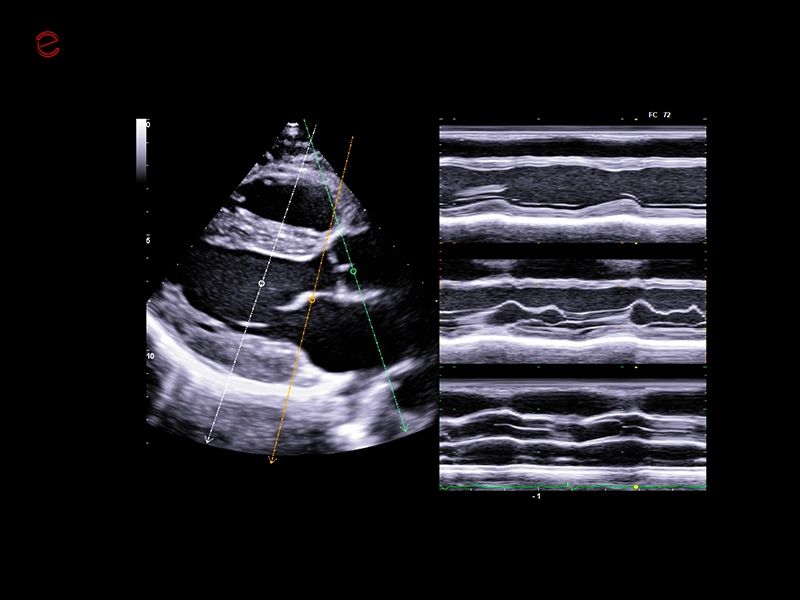

MyLab™X90 - AutoEF Automatic Ejection fraction assessment of the left ventricle

MyLab™X90 - AutoEF Automatic Ejection fraction assessment of the left ventricle